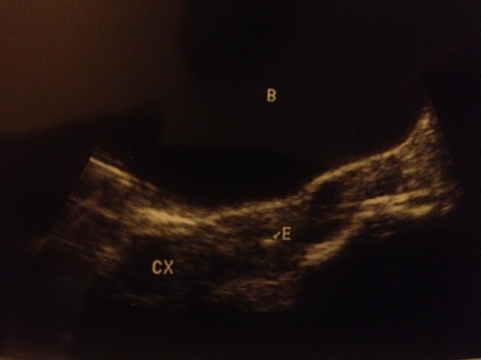

During the embryo transfer, the doctor uses a very small catheter guided by ultrasound to place the embryos inside the uterus. During our transfer, they printed a picture labeled with “B” for bladder, and “E” for embryos (actually the air bubble where the embryos are – they’re too tiny to see), and we got to keep it. I have never had a pregnancy ultrasound picture that I got to keep. All of our pictures before this one were the sorts of things doctors don’t let patients keep: empty sacs or an empty womb where a baby should be.

This picture is different; it’s actual proof that our embryos started out in the right place – proof that we have done absolutely everything in our power to have a baby that is genetically our own. This picture is worth thousands and thousands of words. Words of hope and possibility and life. This picture makes me feel like this could be the first positive step towards holding a baby of my own. It feels like a real pregnancy.